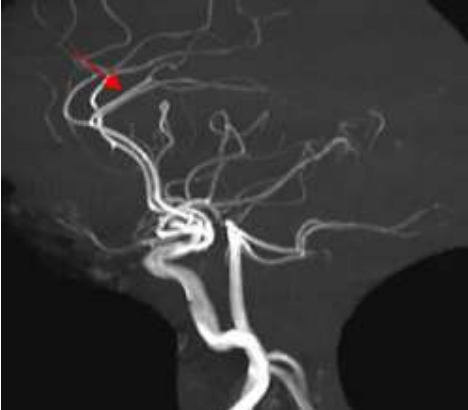

Paciente de 7 anos, sexo feminino, é atendida em unidade de urgência com episódios recorrentes de cefaleia e déficit motor dimidiado temporário. Em investigação complementar realiza estudo angiográfico que demonstra os achados de imagem abaixo.

Enunciado 3028013-1

Baseado no caso e nas imagens apresentadas, assinale a alternativa correta.